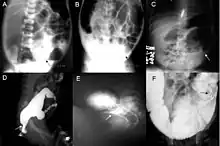

Radiologic findings may also assist with diagnosis.[33] Cineanography (fluoroscopy of contrast medium passing anorectal region) assists in determining the level of the affected intestines.[34]